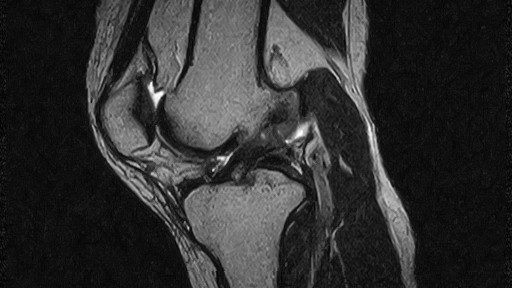

2022年11月12日、キックボクシングの練習中に飛び蹴りをし、左足で着地した際に、左膝をに捻った。 そして、その後も約1時間練習を続けた。 患者は膝が崩れる感覚を覚えた。 11月21日、患者は最初のMRIを受けたが、古いMRIで解像度が低く、診断に有効ではなかった。 12月6日、患者は3回目のMRIを新しいMRI撮影機で撮り、以下の診断を受けた。

前十字靭帯部分断裂

12月7日より、当院のナチュラリゼーション療法をオンラインにて開始し、それを5週間続けた。そして、 2023年1月16日、3回目のMRI検査を行った。

部分断裂により弛んでいた線維は、その緊張を取り戻し、かつ、その直線性も回復させていた。